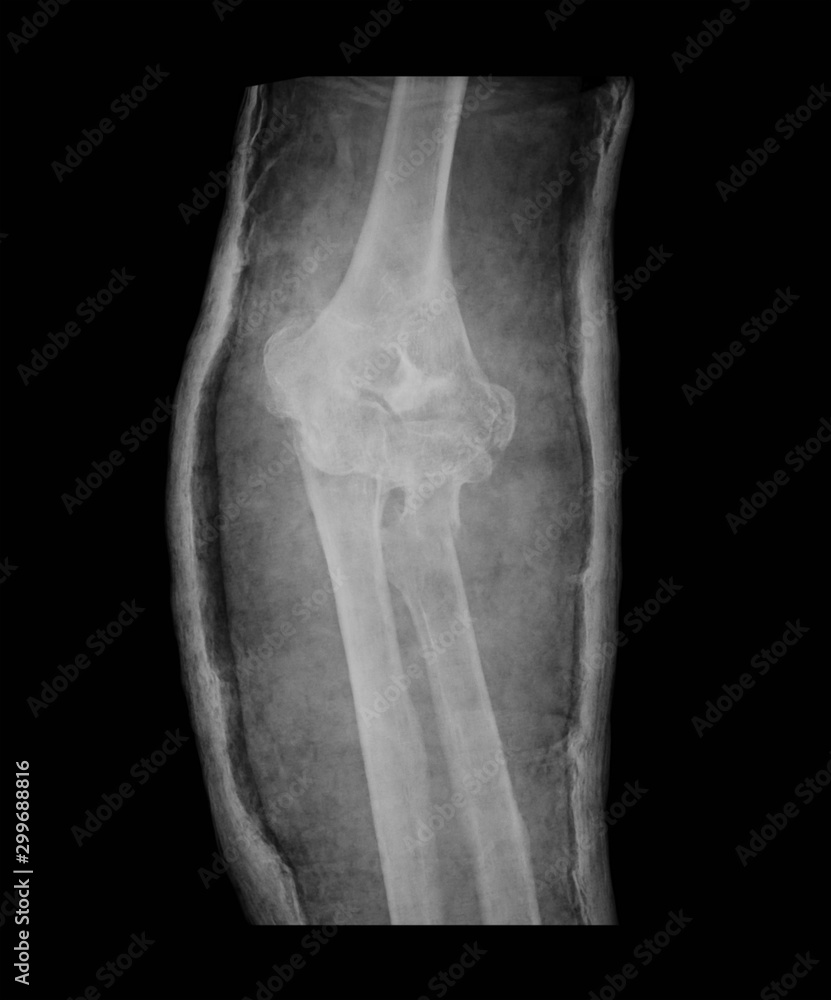

From www.istockphoto.com

Elbow Fracture Xray Ap View Stock Photo Download Image Now Left Elbow Fracture X Ray Surgeons often get ct scans of elbows if they’re trying to. Learn how to diagnose elbow fractures and dislocations with radiographs and ct scans. Learn about the elbow series, a set of radiographs taken to investigate elbow joint pathology, often in the context of trauma. Drawn down the anterior surface of. Check the anterior humeral line: What is the most. Left Elbow Fracture X Ray.